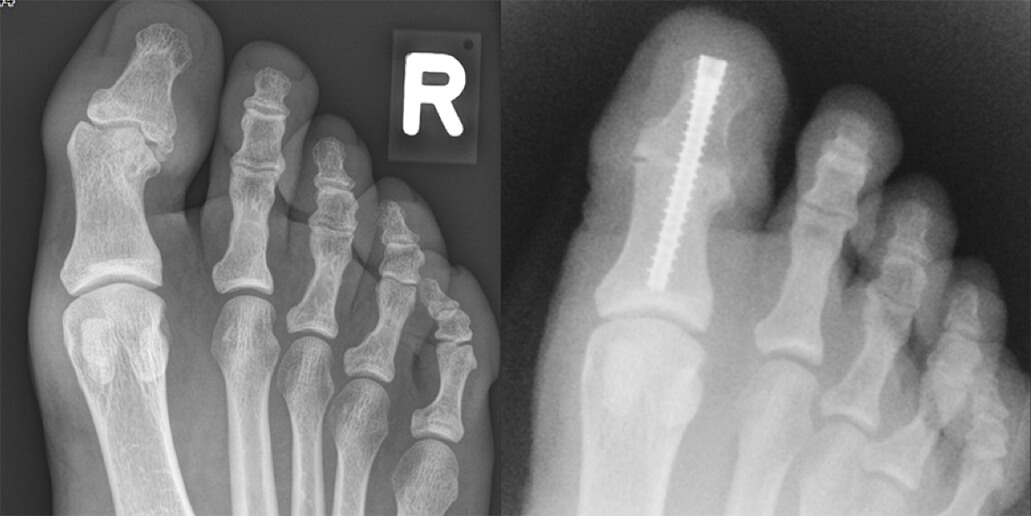

Het vastzetten van het IP-gewricht gebeurt tijdens een dagbehandeling. Verdoving gebeurt met een ruggenprik of onder algehele narcose. De operatie duurt ongeveer een half uur. De chirurg maakt een snee bovenop de teen, en een klein sneetje op de teentop. Het resterende kraakbeen wordt uit het gewricht verwijderd. Daarna worden de botdelen op elkaar geschroefd via de teentop (zie foto). Omdat er wat bot en kraakbeen wordt weggehaald, wordt de grote teen door deze ingreep een paar millimeter korter.

Op de röntgenfoto links ziet u de voet voor de operatie, op de foto rechts de voet na de operatie.

Niet alleen bij een versleten gewricht, maar ook bij een extreem gebogen gewricht wat niet op een andere manier recht te krijgen valt kan het kromme gewricht vast gezet worden. Deze tiener had een kromstand die niet te corrigeren was en die pijnklachten gang als hij schoenen droeg. Ook had hij pijnklachten op het topje van zijn grote teen.